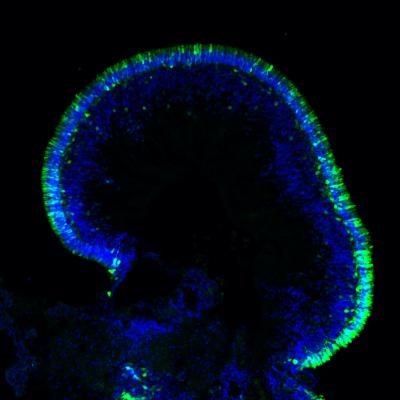

Cross-section of organoid with orderly layers of blue and green colored cells

Human retinal organoid. Credit: Anand Swaroop, Ph.D.